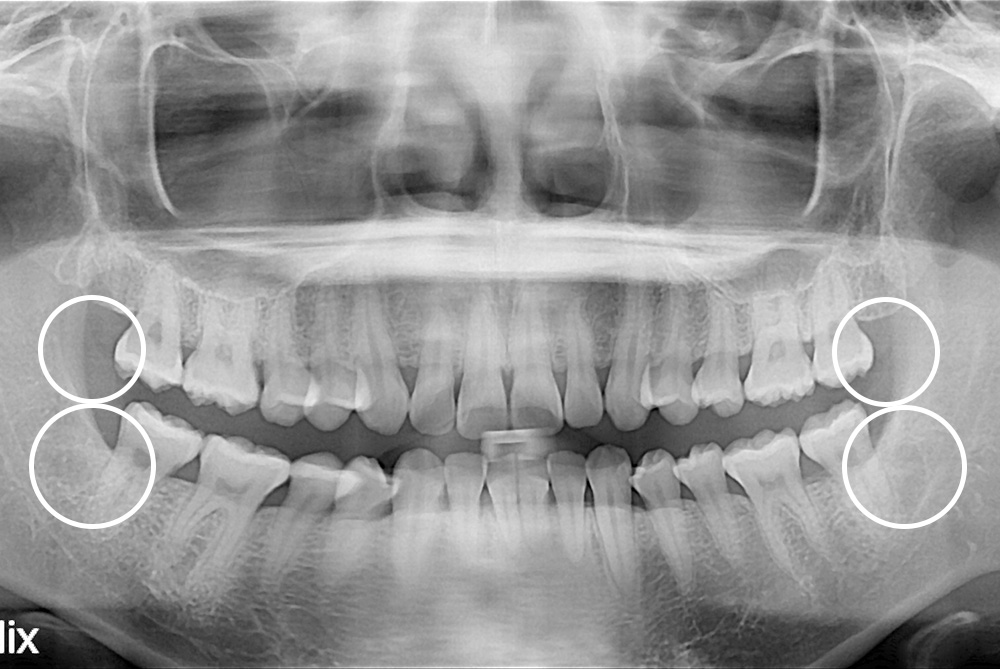

[사랑니] 매복 사랑니 발치

치료후 : 2021-10-25

세종치과는 구강악안면외과학 박사이신 원장님이 발치하는 치과입니다.